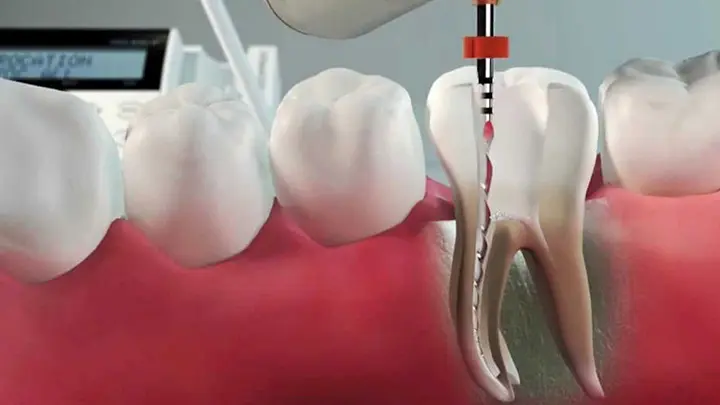

Kliniğimiz Yüksek Kaliteli Ağız ve Diş Sağlığı Hizmetlerini Akhisar ve Çevresine Tek Bir Çatı Altında Vermek Amacıyla 2022 Yılında Kuruldu. Özel Akhisar Prestij Ağız ve Diş Sağlığı Polikliniği Olarak Alanında Uzman Doktorlarımız ile İmplant Tedavileri, Gömük 20 Yaş Diş Çekimi, Botoks Tedavileri, Kist ve Tümör Tedavileri, Çene Eklemi Rahatsızlığı Tedavisi, Genel Anestezi Altında Diş Tedavileri, Gülüş Tasarımı, Zirkonyum Diş Kaplama, Lamine Diş Kaplama, Ortodonti ve Diş Teli Tedavileri, Diş Şeffaf Plak Uygulamaları, Kanal Tedavisi, Diş Protezi, Çocuk Diş Hekimliği, Pedodonti, Diş Eti Tedavileri, Periodontoloji, Diş Röntgen Görüntüleme Alanlarında Ağız ve Diş Sağlığına Ait Tüm Hizmetleri Sunmaktayız.